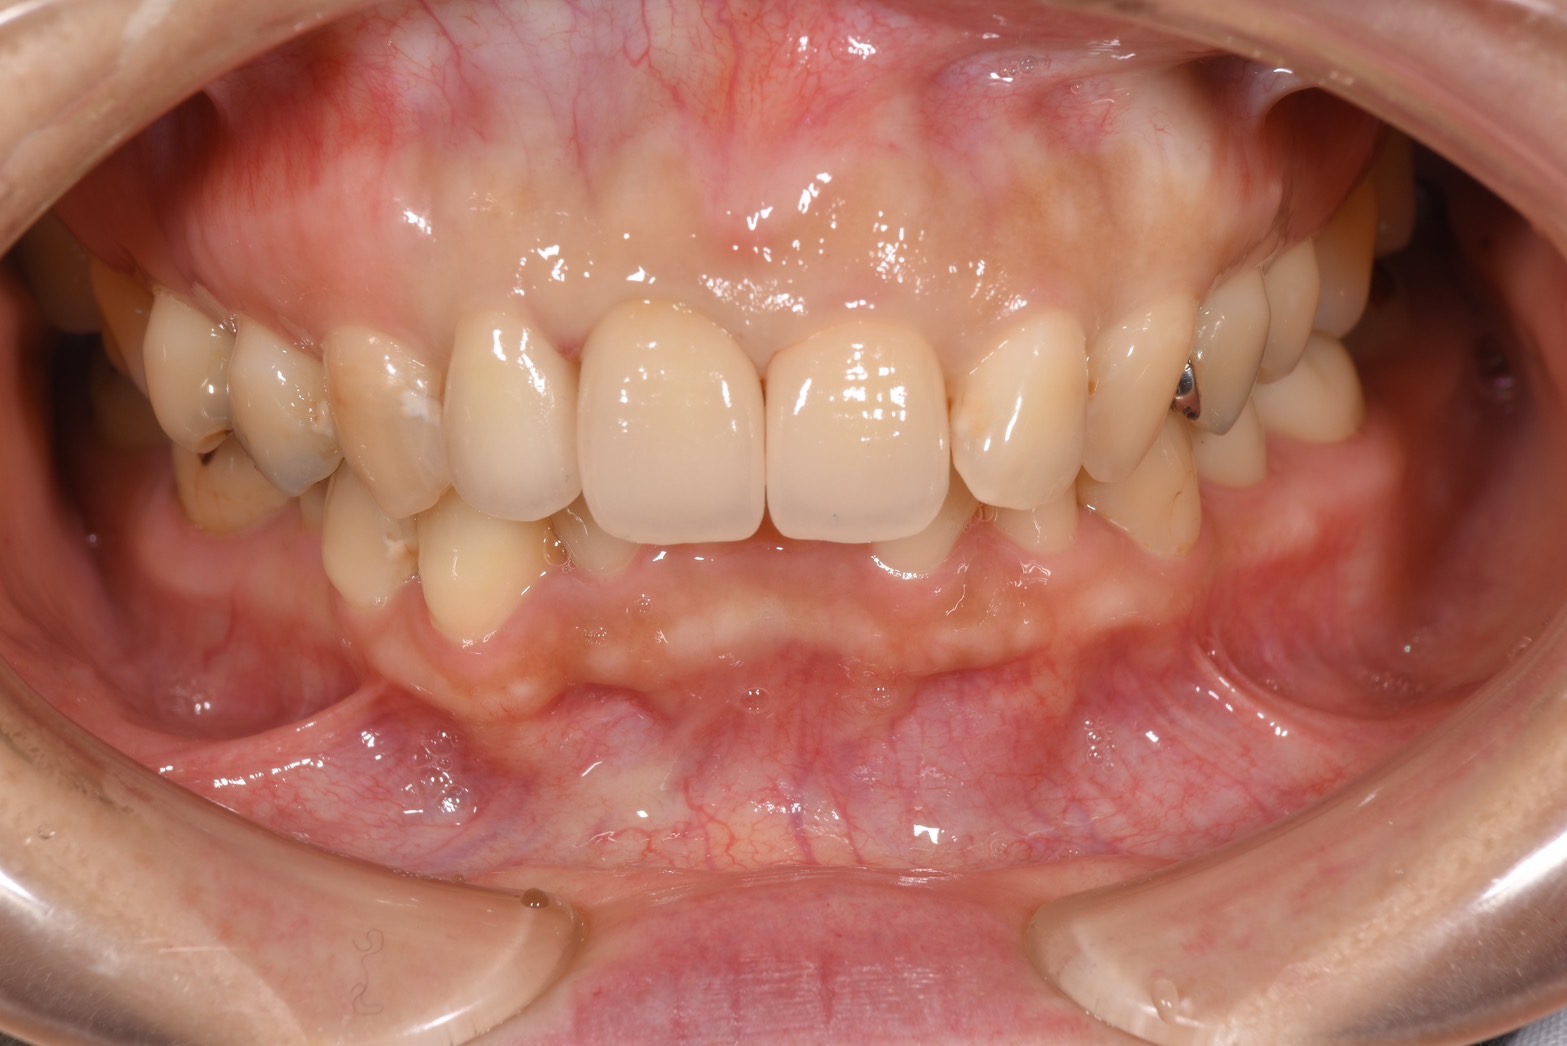

術前

前歯2本がセラミックで治療されているが、右上1番にメタルの土台が使用されているため、歯茎が黒く見える、

また適合不良のため2本とも歯肉に炎症があり、歯肉が赤っぽくなっている。